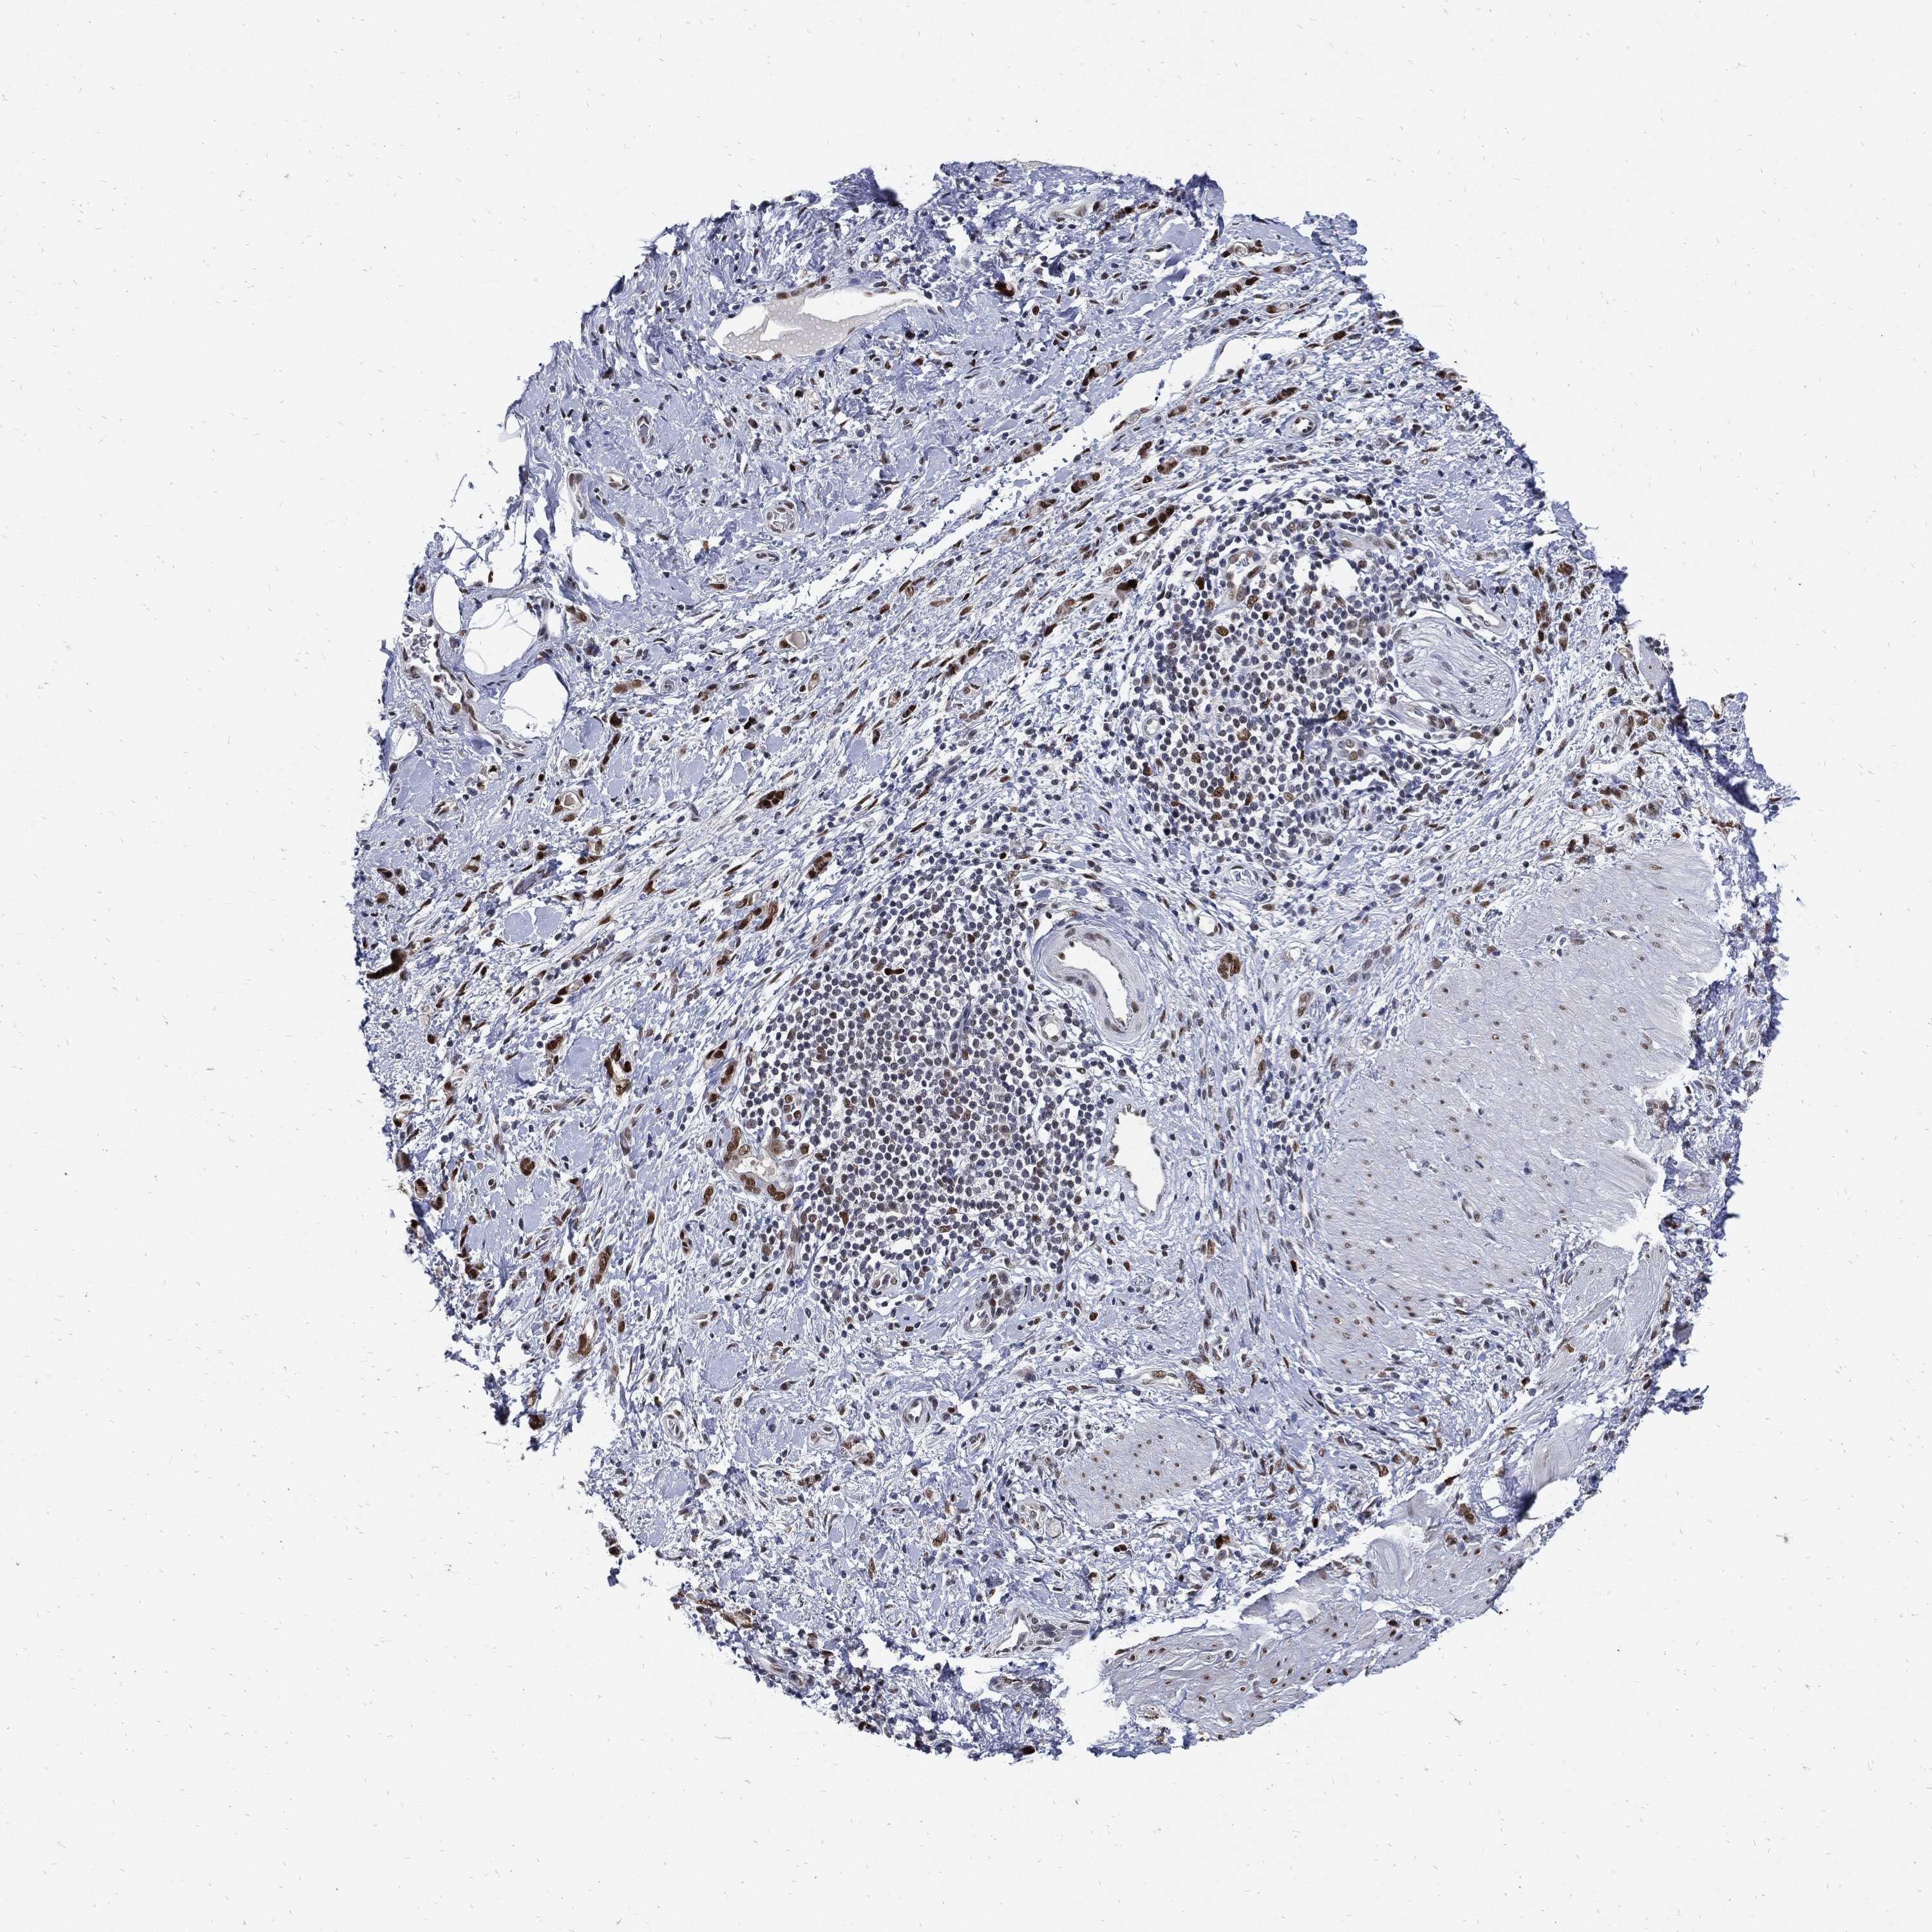

STOMACH CANCER - Protein expressioni

A mouse-over function shows sample information and annotation data. Click on an image to view it in a full screen mode. Samples can be filtered based on level of antibody staining by selecting one or several of the following categories: high, medium, low and not detected. The assay and annotation is described here.

Note that samples used for immunohistochemistry by the Human Protein Atlas do not correspond to samples in the TCGA dataset.

Antibody stainingi

Antibody staining in the annotated cell types in the current human tissue is reported as not detected, low, medium, or high, based on conventional immunohistochemistry profiling in selected tissues. This score is based on the combination of the staining intensity and fraction of stained cells.

Each image is clickable and will lead to virtual microscopy that enables deeper exploration of all samples and also displays staining intensity scores, fraction scores and subcellular localization as well as patient and tissue information for each sample.

Antibody HPA001429

Antibody CAB003836

Antibody CAB080233

Staining

High

Medium

Low

Not detected

Intensity

Strong

Moderate

Weak

Negative

Quantity

>75%

75%-25%

<25%

None

Location

Nuclear

Cytoplasmic/membranous

Cytoplasmic/membranous,nuclear

Adenocarcinoma, NOS

Adenocarcinoma, High grade